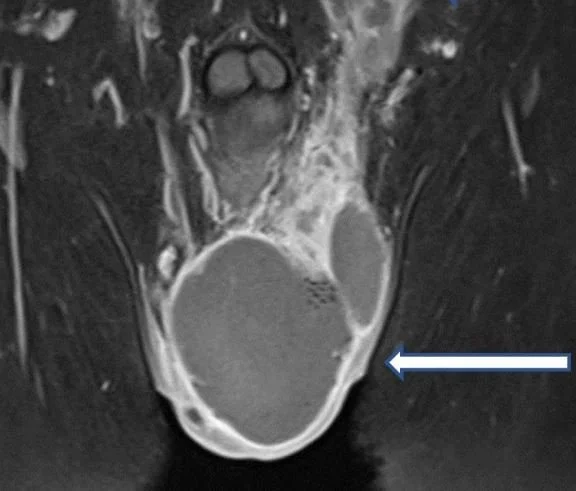

paragonimiasis has been found in a scrotal abscess. It only rarely affects other body part and is usually in the lungs.